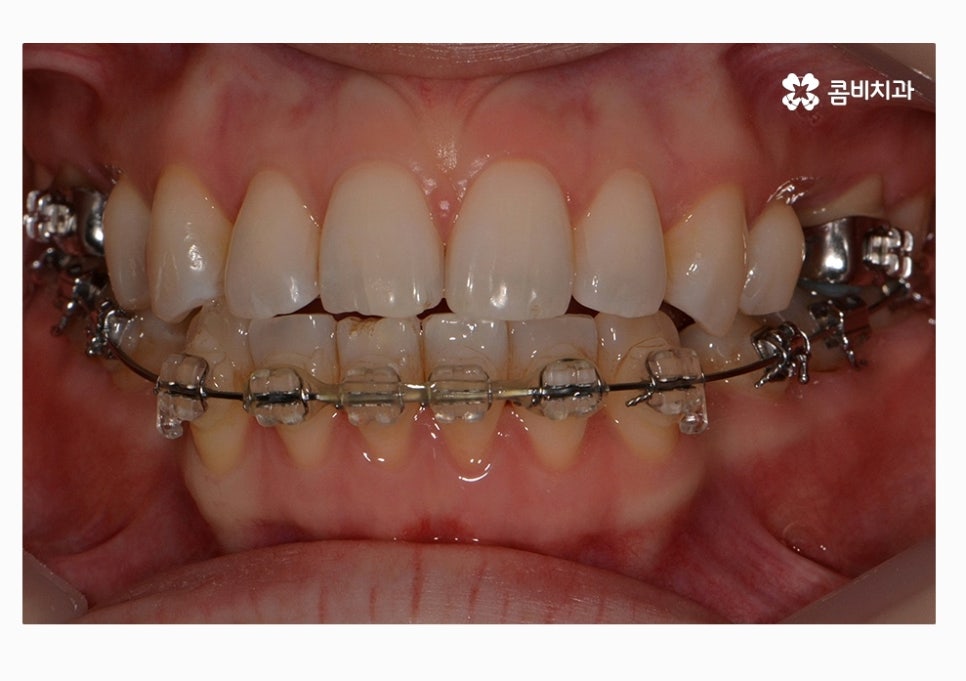

오늘 보시는 콤비교정 치료 케이스가 그러한 경우에 해당하며

정면으로 치열을 볼 때는 비교적 가지런한 편으로

보이지만 자세히 보면 부정교합에 해당한다는 것을 알 수 있어요.

콤비교정은 윗니는 치아의 안쪽에 교정기를 부착하고

아랫니는 치아의 바깥쪽에 장치를 부착하는 방법으로

크게 웃지 않는다면 평소에는 잘 티가 안 나는

심미적으로 우수한 교정 방법이라고 할 수 있어요.

위 환자분의 경우에는 콤비교정의 치료 경과를 보면

아랫니가 정상교합이 되었고 치열도 보다 가지런하게

변화되고 있음을 알 수 있는데요.